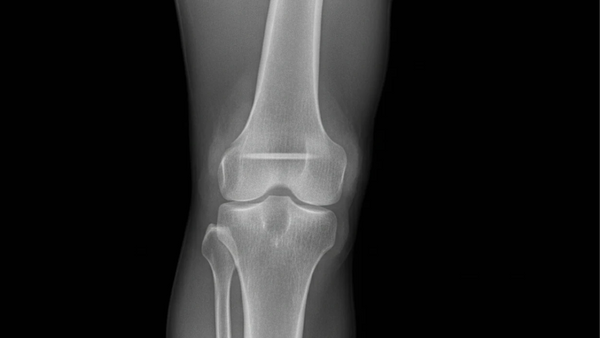

Your body weight plays a significant role in joint health, especially in load-bearing areas like the knees, hips, and spine. Carrying extra pounds increases mechanical stress on these joints, accelerating cartilage breakdown and inflammation.

Every pound of excess weight places up to four pounds of additional pressure on the knees during movement. Over time, this strain contributes to the development or progression of conditions like osteoarthritis. Reducing body weight can significantly lower joint pain and improve overall mobility, especially in the lower limbs.